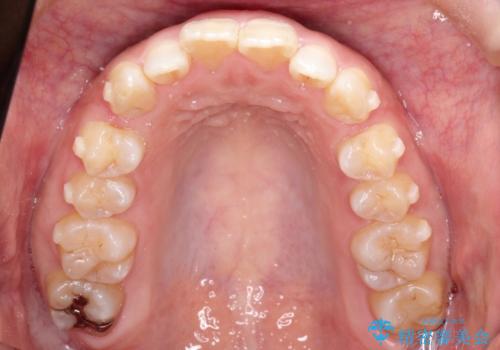

初診時の歯並びの状態としては、上の前歯が下に対して前に飛び出た上顎前突という状態で、前歯は大きく前に飛び出した状態により患者様も口の閉じづらさを感じているとのことでした。また上顎に軽度の叢生(ガタガタ)がありました。

抜歯は行わず上顎の奥のスペースを利用して歯をスライドする方法の他に歯列弓の拡大やディスキング(歯と歯の間の隙間を作る処置)を行い叢生を改善しました。